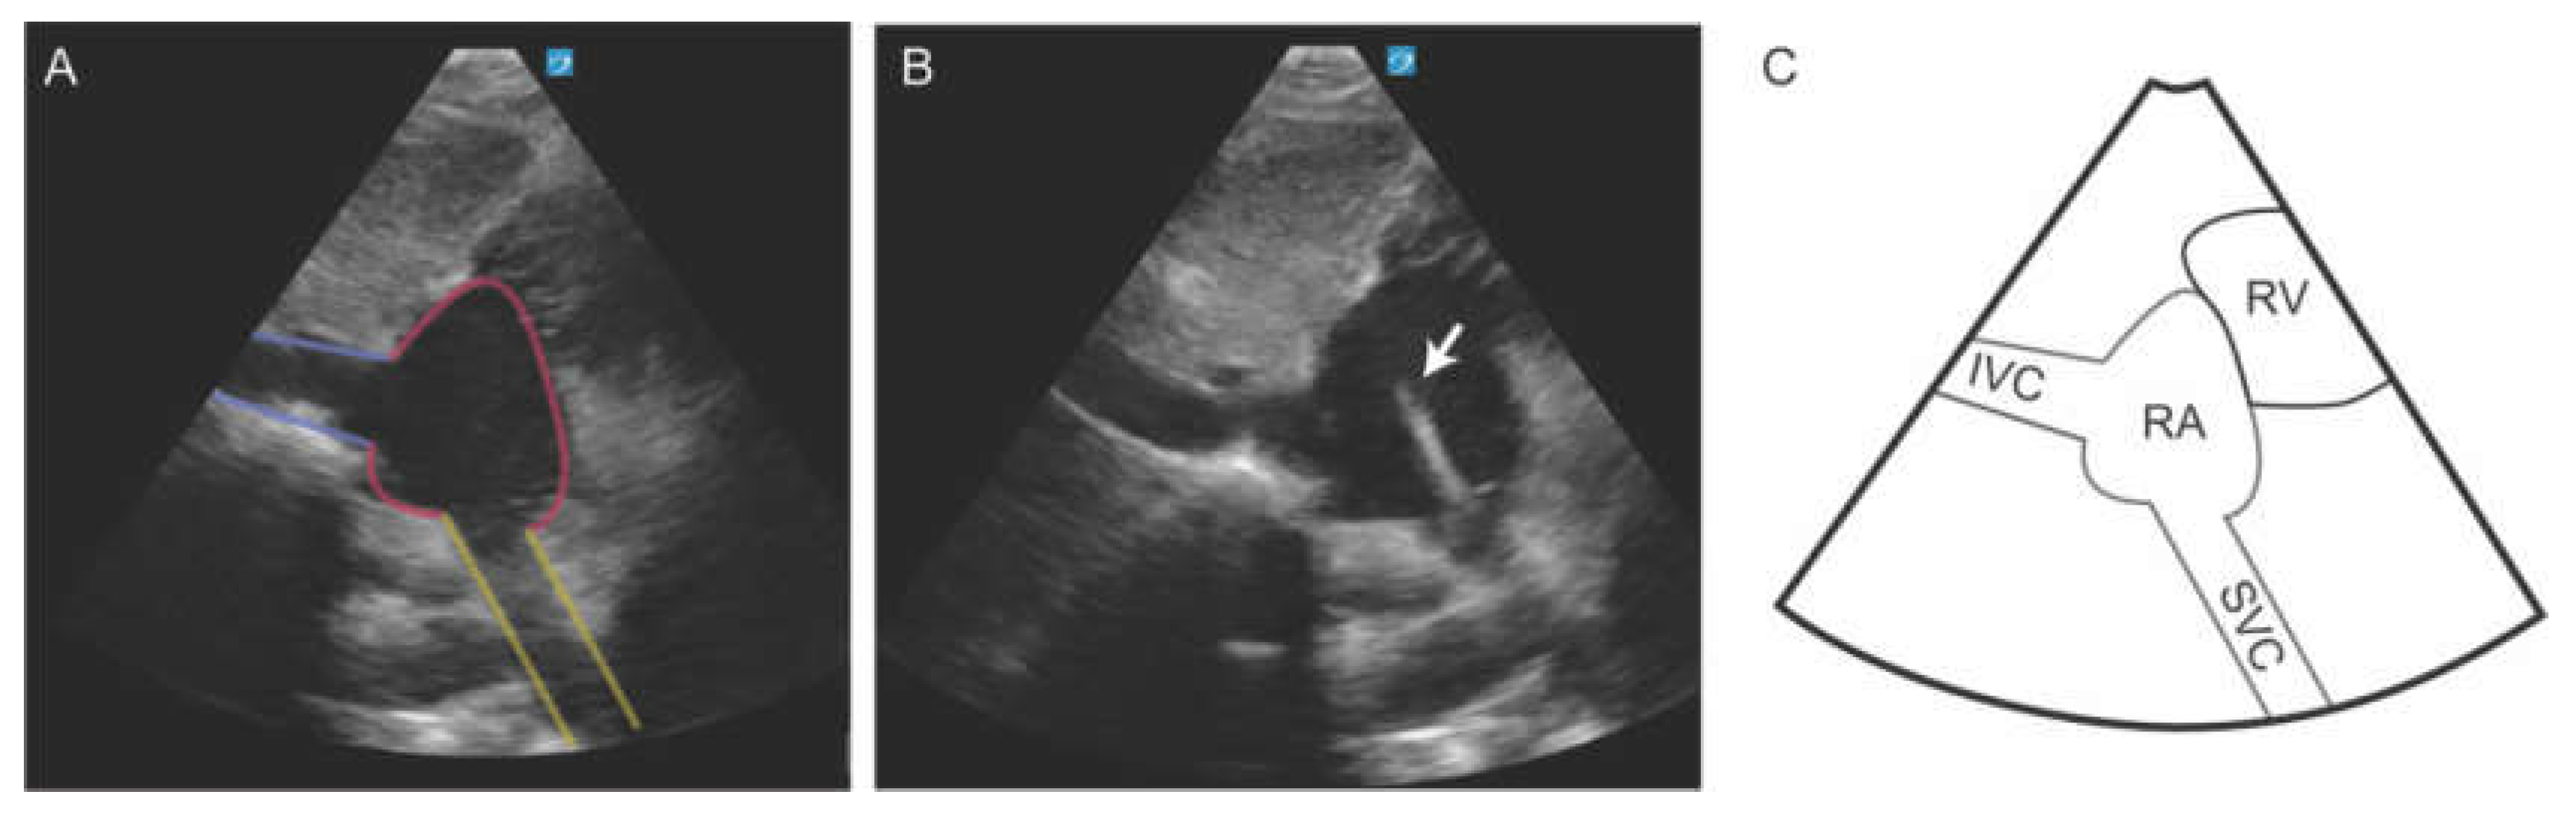

The use of ultrasound for CVC placement and verification has been accepted as standard of care [10,34]. Ultrasound is noninferior to CXR for confirming catheter placement while providing faster results (10 minutes vs 50 minutes), reducing radiation exposure, and lowering healthcare costs [35,36]. CVC placement can be verified using a modified subcostal view that brings the superior vena cava (SVC) and cavoatrial junction (CAJ) into view. This modified view is obtained by first optimizing the long-axis view of the inferior vena cava (IVC). Once the IVC is clearly visualized, the imaging depth should be increased, and the transducer angled cephalad to bring the SVC into the ultrasound sector. In this view, the SVC appears at the bottom of the sector, typically around the 5 to 6 o’clock position, as it enters the right atrium (RA) [37]. This view allows dynamic monitoring of the guidewire, facilitating confirmation of accurate positioning at the CAJ and enabling precise determination of the optimal catheter insertion depth (Figure 8). This method significantly improved success rates (100% vs. 87.5%, p < 0.05) and reduced access times (26.8 ± 12.5 seconds vs. 44.8 ± 54.9 seconds, p < 0.05) [35]. When CAJ views were inadequate, contrast-enhanced ultrasound (CEUS) successfully verified catheter position in 29.7% of cases, offering an alternative for challenging placements [38]. Beyond verification, POCUS is especially useful in live guidance of CVC placement [10]. While it is most used for internal jugular and femoral venous access, POCUS can also aid in subclavian vein cannulation. A study comparing ultrasound guidance to the blind cannulation for subclavian venous catheter placement found that pneumothorax was completely avoided in the ultrasound group (0% vs. 4.9%), with lower rates of arterial puncture, hemothorax, and brachial plexus injury [35,36].

Figure 8. Subcostal bicaval view demonstrating the inferior vena cava (IVC), right atrium (RA), and superior vena cava (SVC). The CVC wire (arrow) is seen emerging from the SVC into the RA.